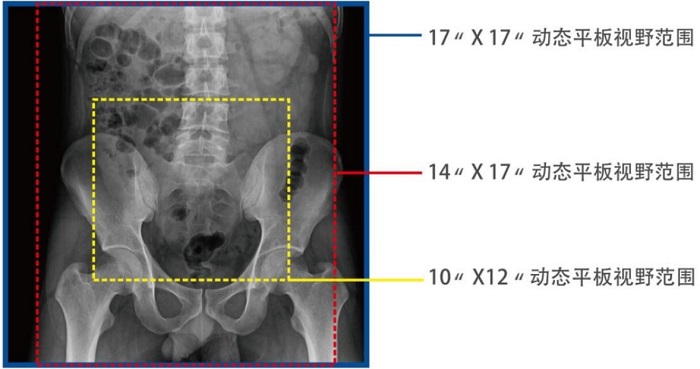

動(dòng)態(tài)DRF在肛腸科檢查中優(yōu)勢(shì)明顯。首先,17×17英寸大幅面成像,對(duì)于食道、胃、腸、結(jié)腸等大范圍成像部位,可一次曝光完成,極大減少了患者的輻射劑量和檢查時(shí)間,且空間分辨率高,與傳統(tǒng)胃腸機(jī)相比,圖像質(zhì)量大幅提升。